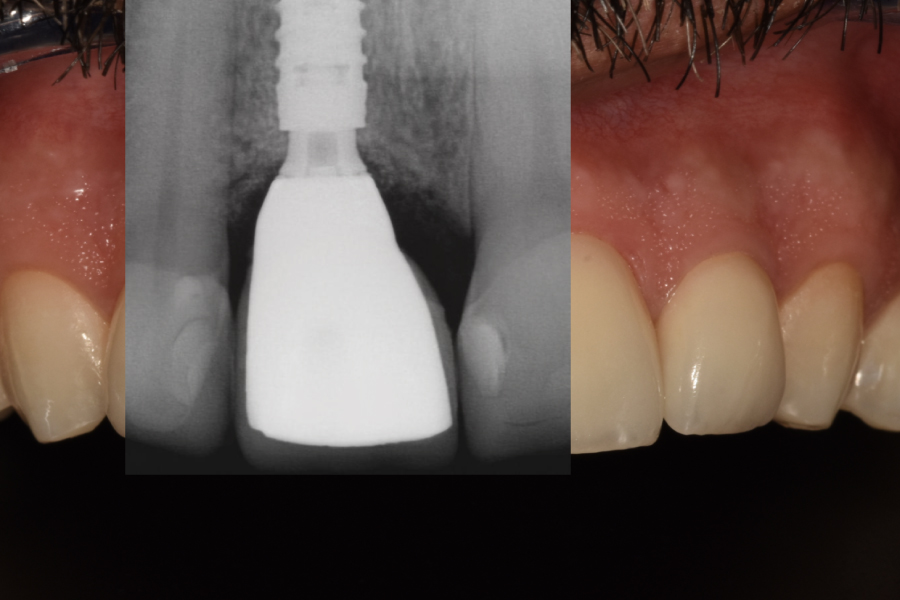

Fase 2: Controles y Segunda Etapa (Mes 4)

- Confirmación de osteointegración (ISQ > 70).

- Restauración definitiva:

Pilar de zirconio ceramizado implanto-soportado monolítico (translucidez media, color A1)

Revisión a los 24 meses

- El injerto óseo xenogénico + ROG permitió cerrar el gap vestibular y prevenir recesión gingival, con resultados estables a 12 meses (5).

- El injerto de tejido conectivo aumentó el grosor y altura del reborde gingival, logrando un perfil de emergencia natural y reduciendo el riesgo de exposición del pilar (6).